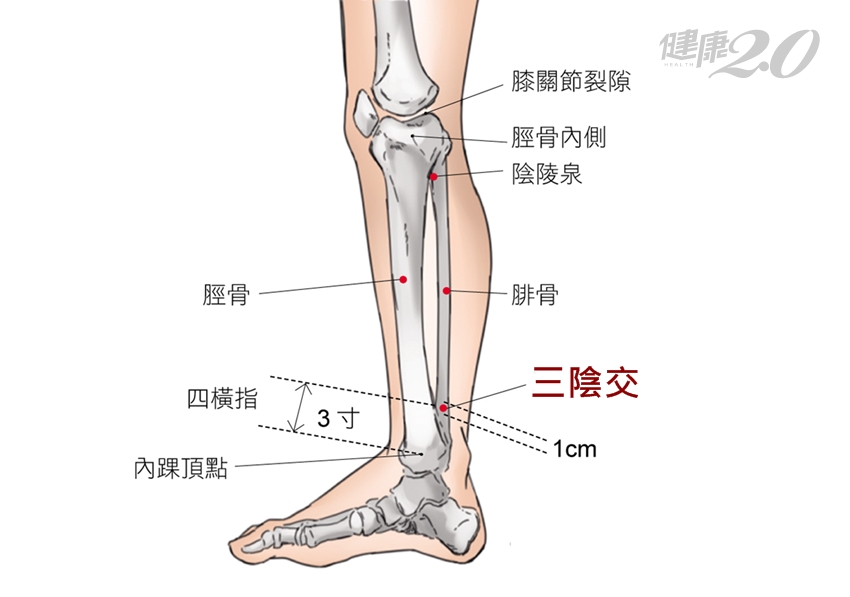

三陰交 調理脾胃、婦科疾病的剋星

中醫說「脾胃是後天之本」、「氣血生化之源」就是說,調養好脾胃可以減少生病,即使生病,恢復的速度也會比較快。脾經,共有21個穴位,而三陰交穴位是足三陰之會的交會穴,分別為足太陰脾經、足厥陰肝經、足少陰腎經,具有補養脾土、幫助運化、通氣滯、疏下焦、調理婦科疾病、祛風溼、通經絡的功效。

三陰交穴位,位於小腿內側、足內踝尖上三寸,脛骨內側後緣方凹陷處。臨床上,三陰交穴位經常運用於女性婦科的疾病治療,例如:子宮功能性出血、月經不調、痛、帶下(陰道泌液體過多,顏色、質地異常)、不孕、治療腹脹、食慾不振、消化不良、腹瀉、腸絞痛、神經衰弱、全身無力等。除了消化不良,我也有一些婦科疾病,因此經常艾灸此穴位來調理身體。